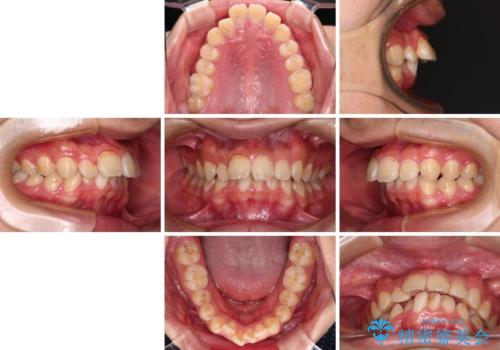

- 深く咬みこんだ前歯と、それに伴い前方に突出した上顎前歯を気にして来院された患者様です。

下顎の歯列は、奥歯が前方に傾斜し、前歯が上顎の歯の付け根に食い込むように内側に傾斜していました。

また、左右の犬歯の位置関係は上顎歯列が前方に位置する咬み合わせとなっており、インビザライン単体で治療するよりは、ワイヤー装置や補助装置を併用した方がより良い仕上がりになることが期待されました。

来院時は学生であったので、補助装置により上顎臼歯を後方に移動させ、下顎歯列はワイヤー装置による傾斜を改善させ、就職のタイミングでインビザラインにて仕上げていくこととしました。